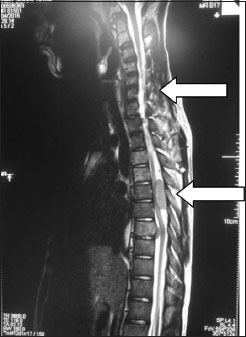

A 16-year-old boy presented to us with history of acute onset of weakness of bilateral lower limbs progressing over 24 h. There was no history of prior trauma or associated fever. On examination, there was weakness of both lower limbs with extensor plantar response. Magnetic resonance imaging spine revealed multiple space-occupying lesions of the spine with loss of cervical lordosis and significant spinal cord compression at the thoracic D4-D7 level [Figure 1] and [Figure 2].

| Figure. 1 Magnetic resonance imaging T2‑weighted sagittal section of the spine showing multiple lesions with Upper left arrow - cervical spine involvement from C3 to C7 spine with reversal of lordosis. Lower left arrow - posterior thoracic lesion causing significant cord compression